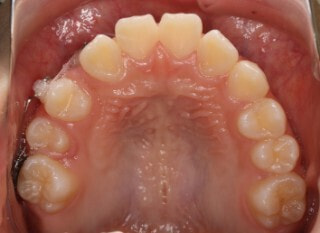

治療前

小児期第一段階

終了時